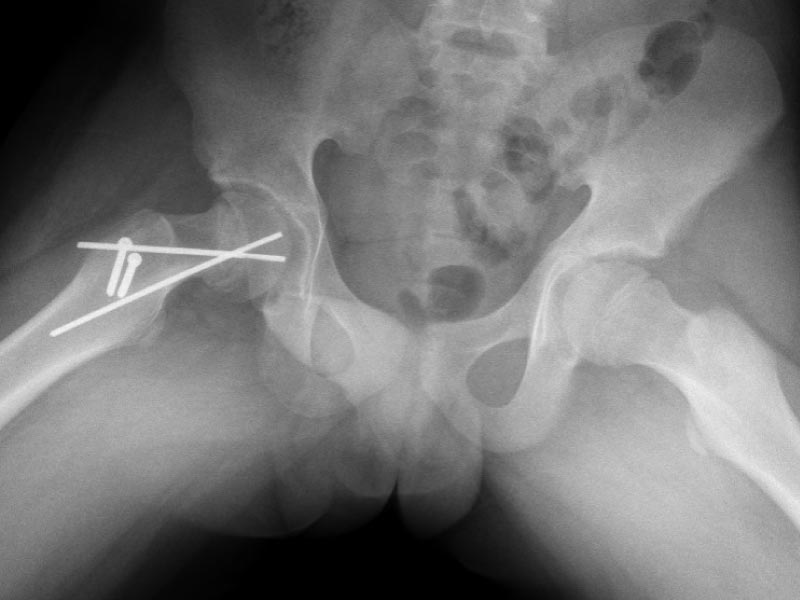

Caso No. 3 - Displasia de cadera derecha con luxación

Preoperación

Posoperación

Displasia de cadera

Diagnóstico: Displasia de cadera derecha con luxación

Tratamiento quirúrgico realizado: reducción abierta, acetabuloplastía y acortamiento femoral

Operada a los 5 años por no diagnosticarse antes, ahora tiene una cadera derecha útil